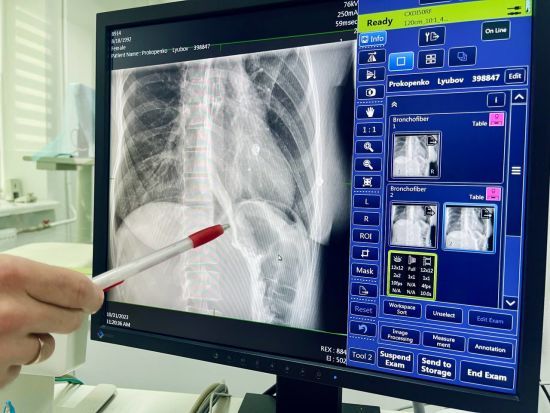

Украинские кардиохирурги зарекомендовали себя в мире так, что даже вопреки войне, к ним едут оперироваться иностранцы

Люди из-за границы, несмотря на войну и отсутствие авиасообщения, безальтернативно выбирают для лечения именно Украину. ru.tsn.ua »